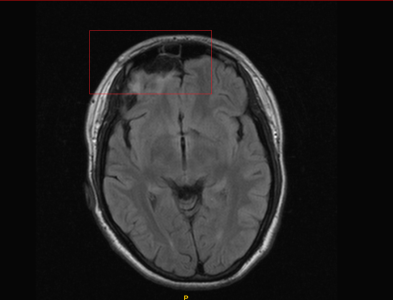

В 2012 году перенес ушиб головного мозга средней степени (на МРТ осталась зона кистозно-глиозных изменений в лобной доле). В течение полутора лет после травмы ничего не беспокоило. Однако спустя полтора года, летом 2013 года, появился симптом - постоянная тяжесть в голове, - который не проходит по сей день, значительно снижая качество жизни.

1. Очаги глиоза.

2. Ассиметрия кровотока по венозным синусам.

Врач нейрохирург сказал, что по сей день не рассосалась кровь (оставшаяся от гематомы после травмы) - видимо, из-за нарушенного венозного оттока, так как снижен уровень метаболизма между клетками мозга в силу застоя крови. Скажите, пожалуйста, есть ли изменения на МРТ в динамике - действительно ли появилось что-то новое на снимках? Действительно ли есть негативная динамика? Или, напротив, что-то рассосалось и динамика положительная? И как мне скоординировать лечение, чтобы избавиться от симптомов?

В 2012 году перенес ушиб головного мозга средней степени (на МРТ осталась зона кистозно-глиозных изменений в лобной доле). В течение полутора лет после травмы ничего не беспокоило. Однако спустя полтора года, летом 2013 года, появился симптом - постоянная тяжесть в голове, - который не проходит по сей день, значительно снижая качество жизни.

1. Очаги глиоза.

2. Ассиметрия кровотока по венозным синусам.

Врач нейрохирург сказал, что по сей день не рассосалась кровь (оставшаяся от гематомы после травмы) - видимо, из-за нарушенного венозного оттока, так как снижен уровень метаболизма между клетками мозга в силу застоя крови. Скажите, пожалуйста, есть ли изменения на МРТ в динамике - действительно ли появилось что-то новое на снимках? Действительно ли есть негативная динамика? Или, напротив, что-то рассосалось и динамика положительная? И как мне скоординировать лечение, чтобы избавиться от симптомов?